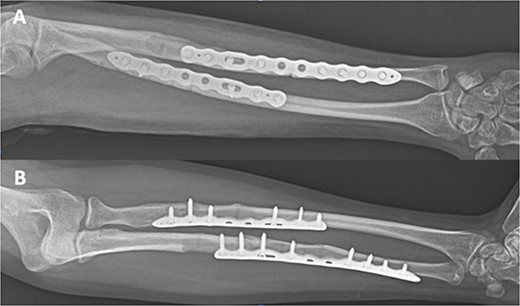

A 32-year-old male was referred to the emergency room after a sport accident. Fourteen months previously, he successfully underwent osteosynthesis with two 3.2 mm stainless steel locking plate (Trimed Elbow Forearm System™, CA, USA) for a radial (six-holes) and ulnar (seven-holes) shaft fractures after a sport accident. On admission, X-rays revealed a NPPIF of both forearm bones (Fig. 1), classified as P1A type [2]. The fracture was just distal to the edge of the last screw of both plates. The patient underwent both hardware removal, reduction of the fractures and fixation using two 3.5 mm longer titanium dynamic compression plate for the radial (eight holes) and ulnar (10 holes) shaft fracture (Stryker Corporation Kalmazoo, MI, USA). After that, the patient was referred for physical therapy and rehabilitation. A total of 3 months after surgery, complete bone healing was observed (Fig. 2). At final follow-up, 36-months after surgery, the patient’s elbow extension and flexion was from 0° to 130°, wrist pronation and supination was from 90° to 75°, and wrist flexion and extension were 75° and 70° were completely painless. His grip strength was 93% that of the opposite hand.

Type P1A fracture—well healed original fracture with NPPIF of both forearm bones distal to the tip of the implant.